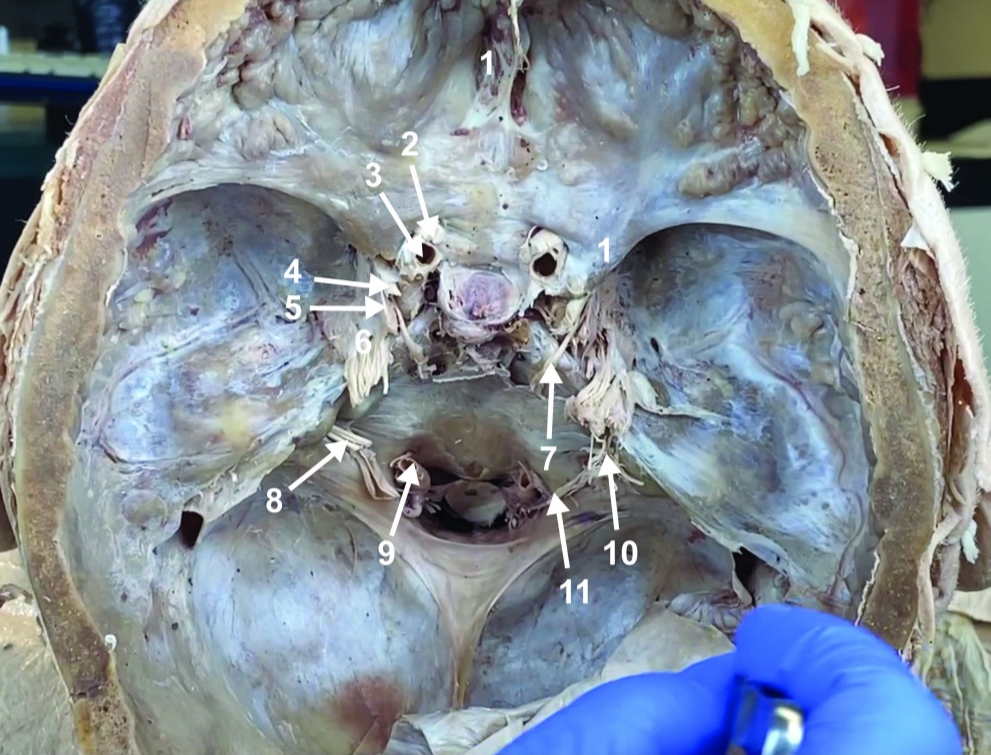

Foramen magnum

ID structure

Foramen ovale

ID structure

Foramen spinosum

ID structure

Cribiform plate

ID structure

Optic n. (CN II)

ID structure

Internal carotid a. (ICA)

ID structure

Occulomotor n. (CN III)

ID structure

Trochlear n. (CN IV)

ID structure

Trigeminal n. (CN V)

ID structure

Abducent n. (CN VI)

ID structure

Facial and vestibulocochlear n. (CN VII and VIII)

ID structure

Vertebral a.

ID structure

Glossopharyngeal and vagus n. (CN IX and X)

ID structure

Root of spinal accessory n. (root of CN XI)

ID structure

Ophthalmic division of CN V (CN V1)

ID structure

Maxillary division of CN V (CN V2)

ID structure

Mandibular division of CN V (CN V3)

ID structure

Foramen rotundum

ID structure

Foramen ovale

ID structure

Trochlear n. (CN IV)

ID structure

Abducent n. (CN VI)

ID structure